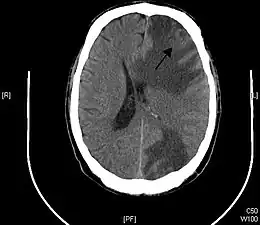

Description de l'image Brain - CT scan - Metastatic pulmonary adenocarcinoma Case 239 (7603361920).jpg.